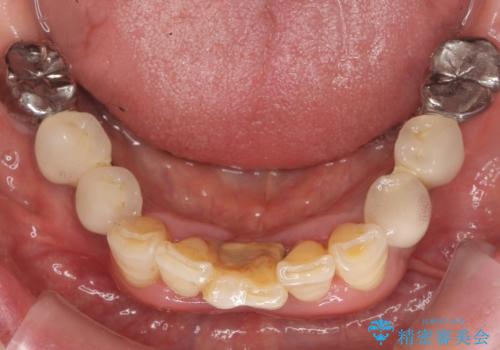

- 上下の前歯が抜けそうだとのことで来院されました。

精査したところ、動揺の著しい上下の前歯は重度の歯周病により保存不可能と判断しました。

ブリッジ、インプラント、義歯の選択肢の中で上下前歯ともにブリッジをご希望されました。

抜歯後歯肉の治癒を十分に待ったのち、ブリッジによる補綴治療を行いました。